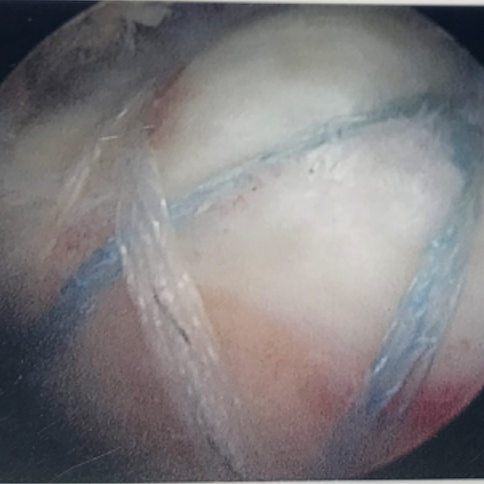

The completed Suture-Bridge tendon repair.  The tendon is firmly snugged down against

the bone footprint of the humerus to optimise the chances of healing